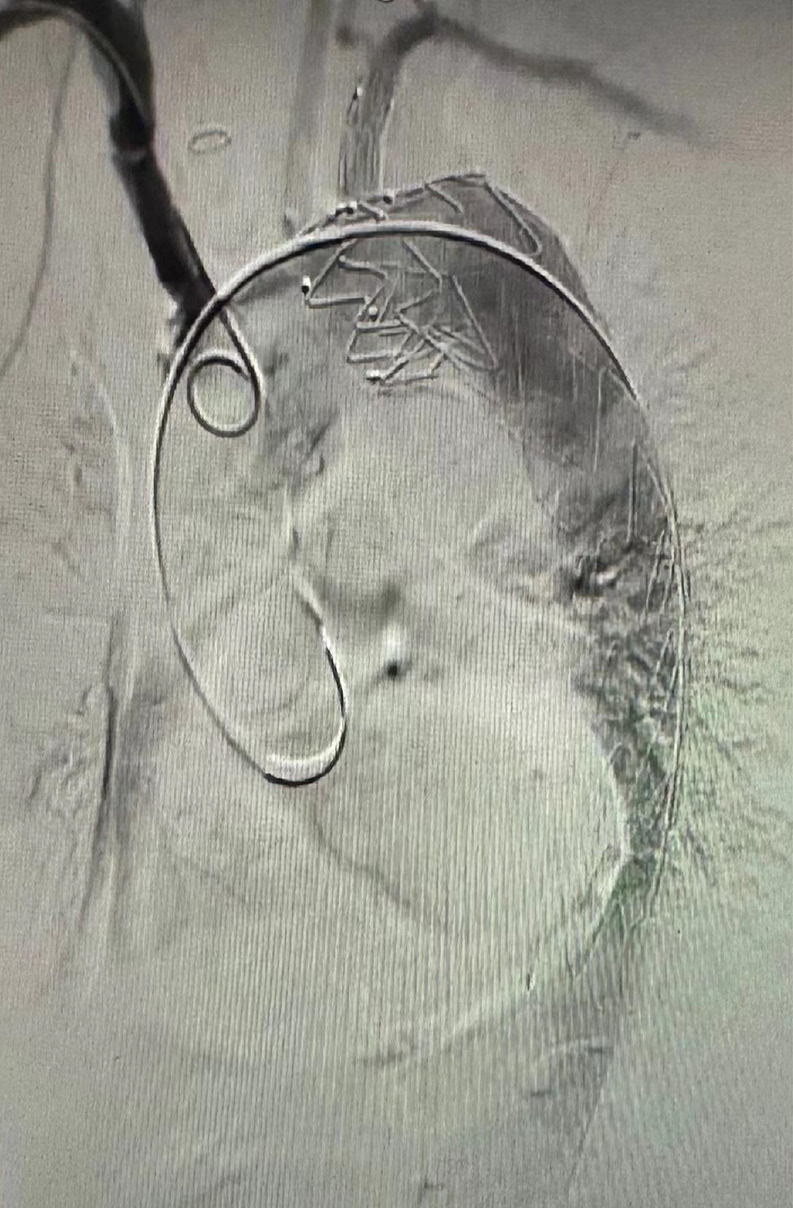

Guidewire and stent placement: After establishing vascular access from the left brachial artery to the right femoral artery, a transverse incision was made in the right inguinal region, and the femoral artery was dissected. The selected Castor stent graft was then inserted through the right femoral artery, with placement guided by real-time imaging. The direction-turnover technique was utilized to ensure that the stent fenestration aligned precisely with the aortic arch branches, with the stent automatically flipping to the correct position upon advancement. Re-angiography confirmed the positioning of the stent, showing unobstructed branch arteries and complete lesion coverage (Figure 3).

Unwrapping technique for guidewire management: To avoid guidewire entanglement, the unwrapping technique was applied when necessary. This involved retracting the stiff guidewire into the stent sheath to reduce tension and then gently guiding the branch wire to the LSA to maintain optimal placement. This step was crucial to ensure proper orientation and secure stent deployment.

To optimize the placement of the Castor stent, we employed 2 innovative techniques: the direction-turnover technique and the unwrapping technique. The direction-turnover technique, proposed by Professor Qingsheng Lu from Changhai Hospital, leverages spatial inversion to control the stent’s fenestration orientation during deployment.19 As depicted in Figure 5, the surgeon holds the anterior grip at the 6 o’clock position without rotation, ensuring that the white marker aligns perpendicularly to the ground (Figure 5A). This alignment ensures that the fenestration remains correctly positioned as the stent advances through the aortic arch (Figure 5B). Upon reaching the ascending aorta, the fenestration automatically flips to the 12 o’clock position, aligning with the branches of the aortic arch (Figure 5C). This transformation simplifies the complex 3-dimensional alignment challenge, enabling a more intuitive and accurate stent placement.

The unwrapping technique, used to address guidewire entanglement, involves retracting the stiff guidewire into the stent sheath while maintaining gentle tension on the branch guidewire (Figure 6). This method allows the branch stent to enter the LSA unobstructed, thus preventing potential cerebral ischemia and reducing the risk of deployment issues. These complementary techniques reduce procedural complexity, improve safety and enhance the reliability of Castor stent implantation, thereby making the procedure more accessible to surgeons across a range of experience levels.